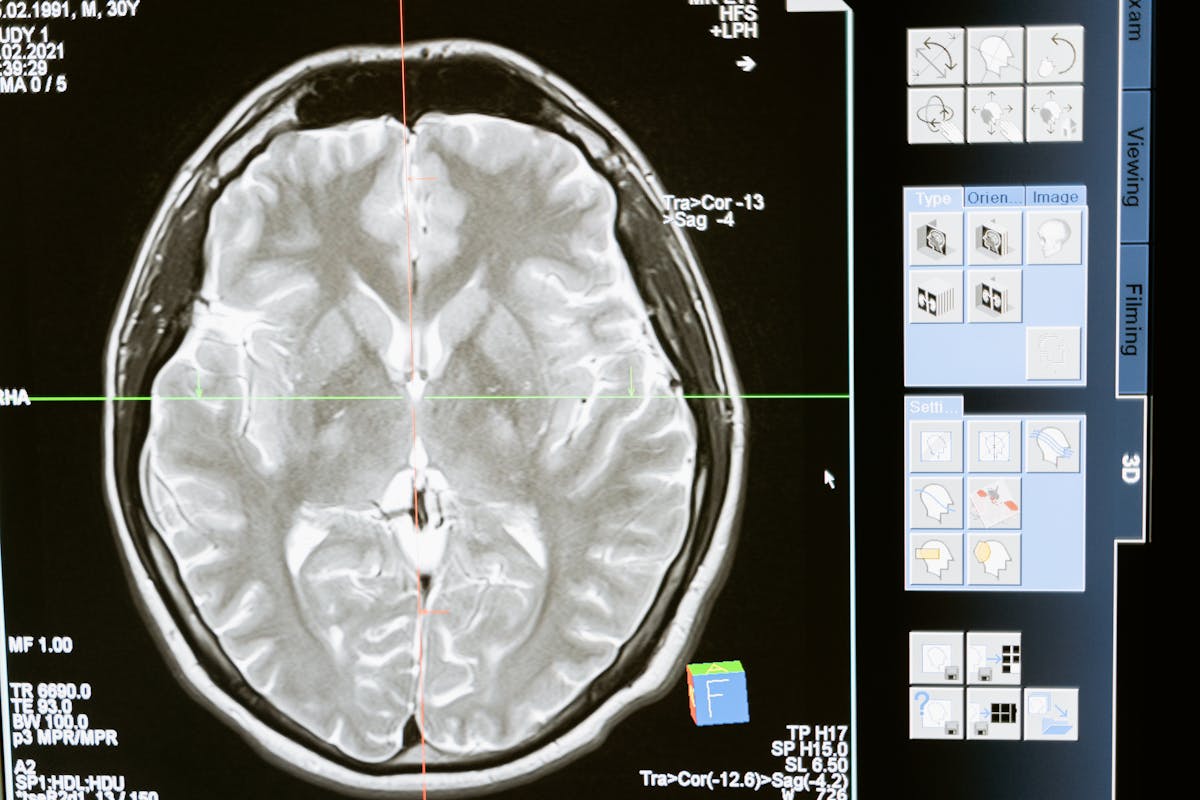

Your hippocampus is the brain's memory encoding center. It takes raw sensory experience, tags it with context (when, where, who), and bundles it into something retrievable. The endocannabinoid system β€” your brain's natural cannabis-like signaling network β€” plays a critical role in this process, particularly in a function called pattern separation: the ability to distinguish between similar but different experiences.

THC, the primary psychoactive compound in cannabis, binds to the CB1 receptors in the hippocampus and essentially turns down the precision on pattern separation. Instead of encoding "I saw the words bed, rest, pillow, tired, dream" as five discrete items, your brain encodes a gist β€” "stuff about sleeping" β€” and when asked to recall the list, it reconstructs from the gist rather than from specific memory traces.

Reconstruction from gist is where false memories live. Your brain says: "The topic was sleep. 'Sleep' is the most obvious sleep-related word. I probably saw it." Except you didn't.

This isn't unique to THC β€” alcohol, sleep deprivation, and even just normal aging can increase gist-based processing. But the study suggests THC is particularly effective at it, possibly because of how directly it targets the hippocampal circuits responsible for encoding specificity.